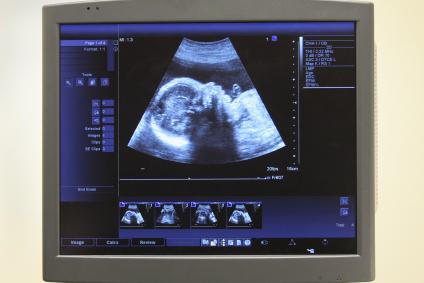

Fetal monitoring occurs throughout a pregnancy, and it involves doctors and nurses checking on the baby’s vital signs, especially the heart rate. It is common in every pregnancy, and may occur often in high-risk pregnancies. External fetal monitoring involves placing a device on the mother’s stomach to listen to the baby’s heartbeat. By listening the doctors can look for patterns that demonstrate the fetus is healthy and developing normally.

Internal fetal monitoring is more invasive and involves placing an electrode device on the fetus directly. The device enters the mother’s cervix and attaches to the fetus’s scalp. Although this sounds harmful, it is more accurate in determining if the baby’s heart rate is stable and healthy. An internal monitor is only done after a women’s has a ruptured her membrane. The risks associated are few and include slight bruising to the baby’s scalp and some minor discomfort for the mother.